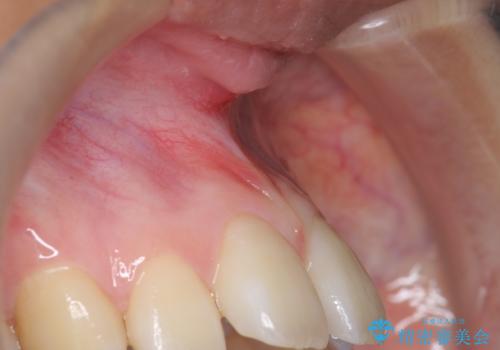

上顎前歯の隙間と出っ歯の一因は上唇小帯と呼ばれる上唇と歯茎を結ぶ線維性の付着によるものであり、矯正を行っても後戻りのリスクが高いことから、矯正前に上唇小帯の切除を行いました。

上唇小帯とは上唇と歯茎を結ぶ線維性の付着のことです。上唇小帯の付着位置が前歯に近いと今回のケースのように正中離開(前歯の隙間)の原因となります。